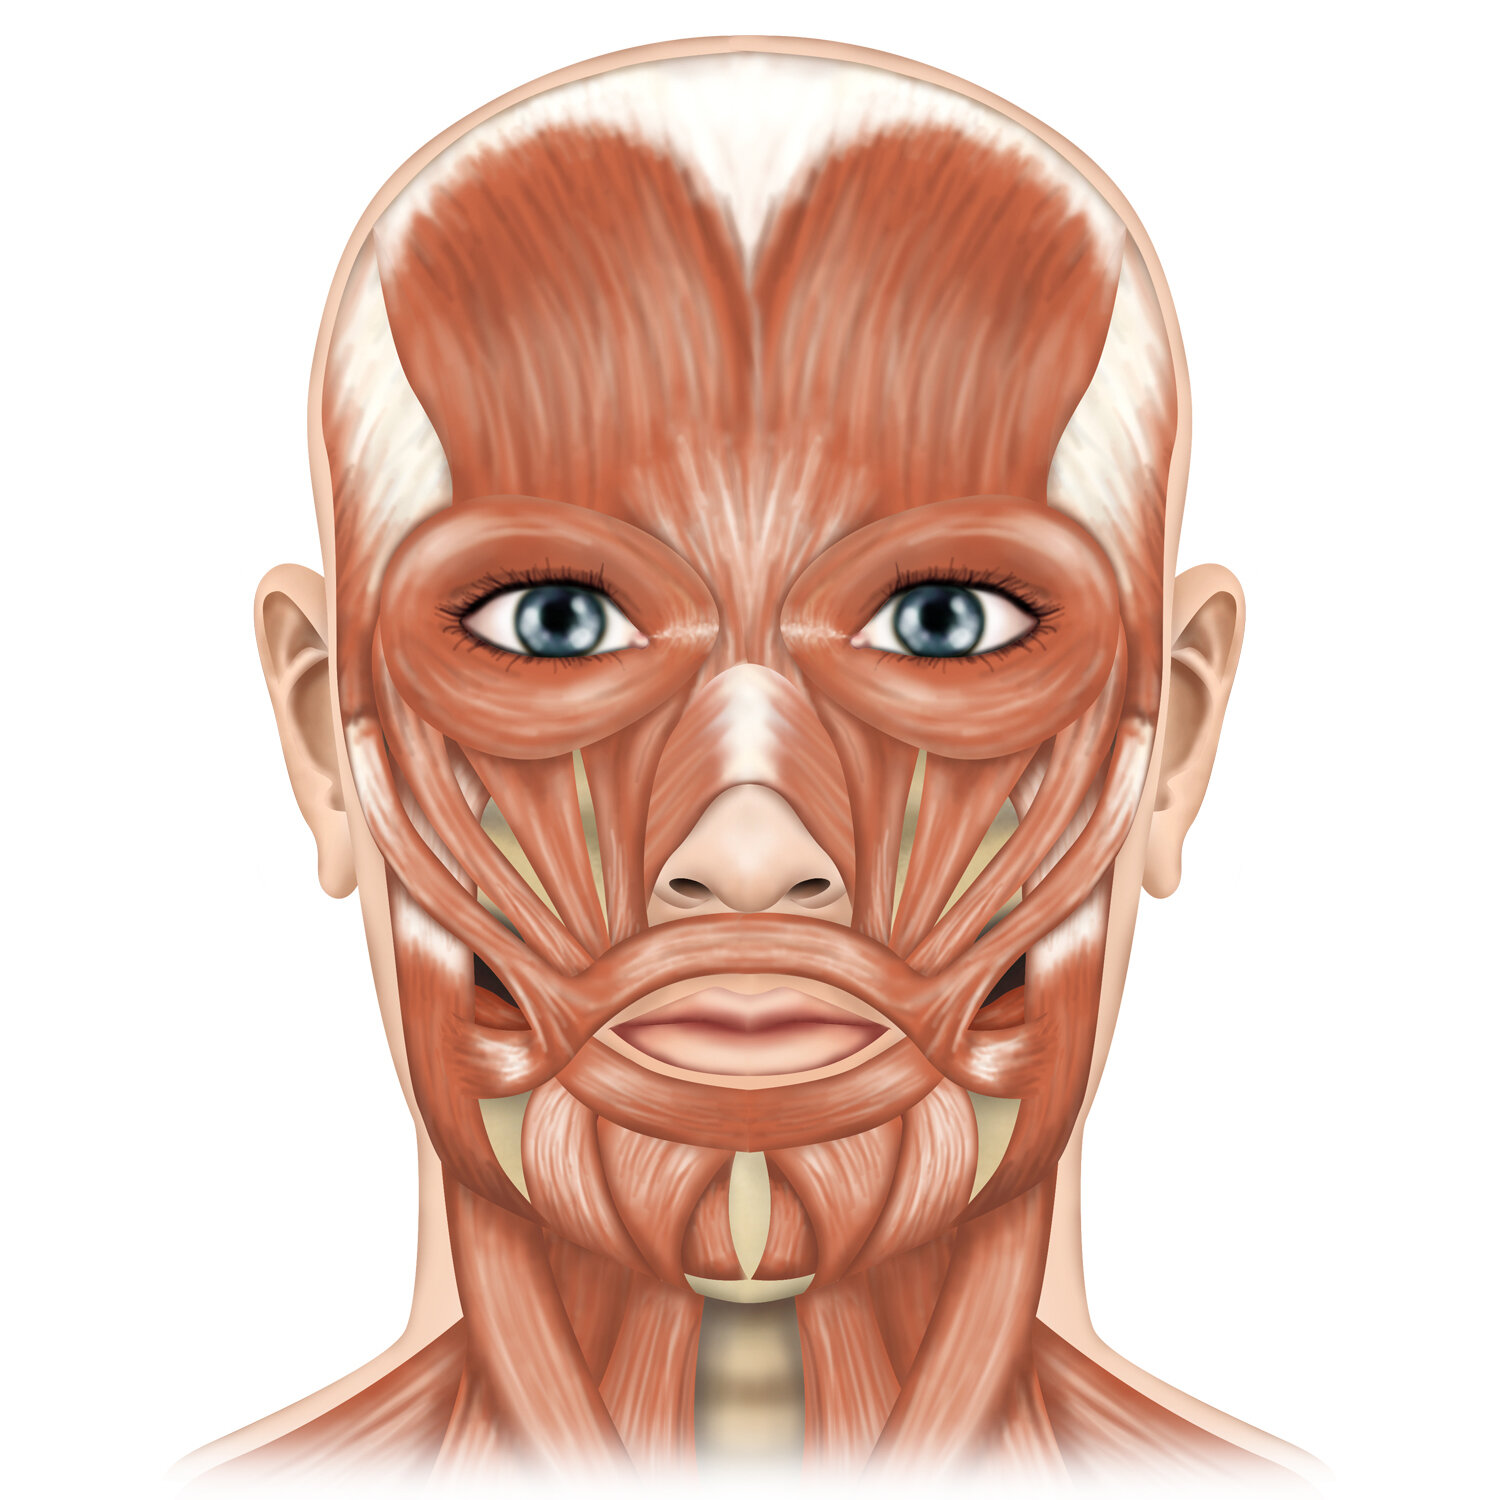

![Facial musculature]()

Facial musculature